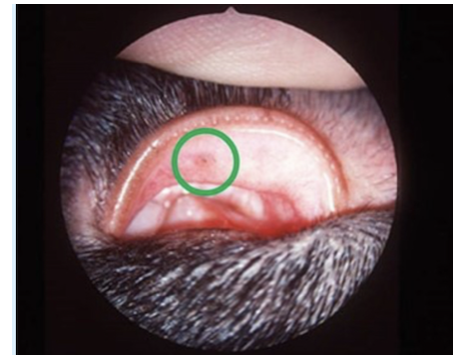

Was ist in der folgenden Abbildung markiert?

Dies ist eine Katze mit einem dendritischen Ulkus. Der fluoreszinpositive Ulkus verläuft linear mit Verzweigungen.

Für welche Infektion ist dies Bild pathognomonisch?